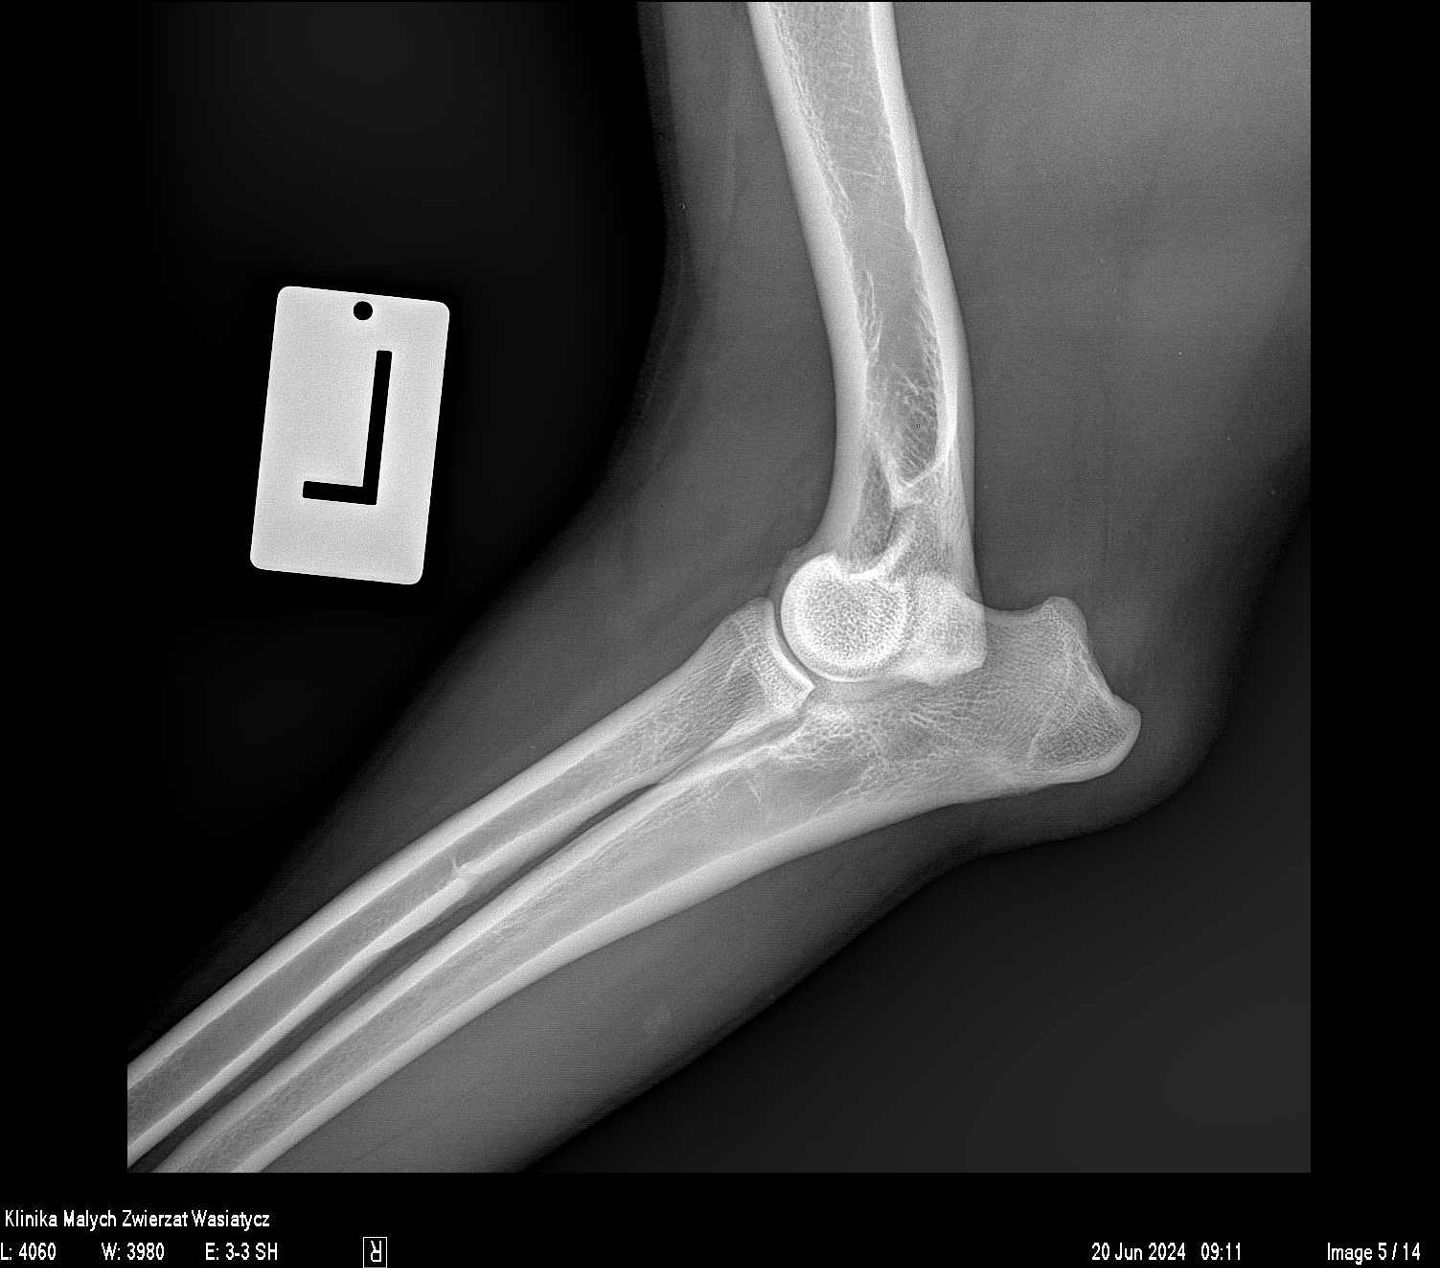

W naszej klinice pracownia rentgenowska stanowiła zawsze bardzo ważne miejsce diagnostyczne. Jako placówka specjalizująca się w ortopedii staramy się zapewnić najwyższą jakość zdjęć rtg, zarówno w zakresie dokładności ułożeń jak i parametrów ekspozycji.

Obecnie, w naszej pracy wykorzystujemy najwyższej klasy sprzęt rentgenowski hiszpańskiej firmy Initech, który został specjalnie skonfigurowany zgodnie z naszymi potrzebami. Jest to również system radiologii bezpośredniej.

Rocznie w naszej klinice wykonywanych jest prawie 20 000 zdjęć rentgenowskich. Każde z nich jest wykonywane przez stale doskonalących się specjalistów, analizowane przez wysokiej klasy lekarzy weterynarii, w tym również specjalistów radiologów. Wszystko to sprawia, że badanie rtg dostarcza maksymalną ilość informacji, która potrzebna jest w procesie diagnostycznym.